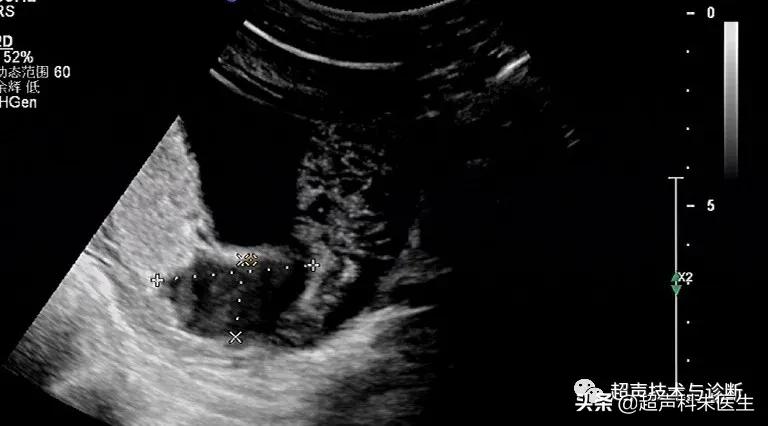

出现绒毛膜下血肿的孕妇,仅有20%会出现阴道不规则流血或下腹部疼痛的症状,而其余大多数绒毛膜下血肿是在超声检查中发现的,其超声表现为:子宫壁和胎膜(或孕囊)之间的无回声区,多位于胎盘下缘至宫颈内口间,以弧形或新月形多见,若血肿较多或血肿形成时间较长时,内可见点、絮状弱回声及条带状强回声,彩色多普勒超声检查:血肿内无血流信号。

根据绒毛膜下血肿的大小和范围,可对其进行定量分型:①小型血肿:妊娠囊周围绒毛膜下血肿的长度小于妊娠囊周长的20%;②中型血肿:妊娠囊周围绒毛膜下血肿的长度为妊娠囊周长的20~50%;③大型血肿:妊娠囊周围绒毛膜下血肿的长度大于妊娠囊周长的50%,或血肿的容积(长x宽x高÷2)>30ml。

接下来我们来看看具体病例: